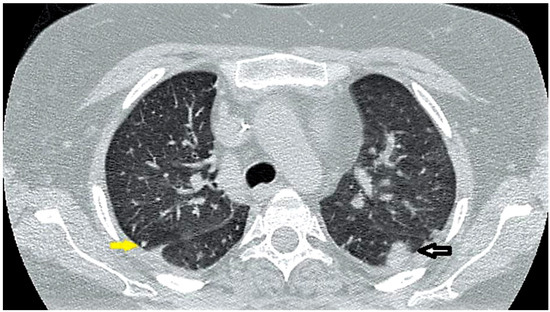

Case report